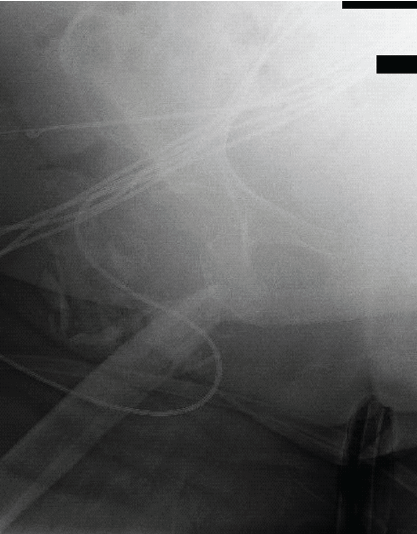

The patient had active extravasation from the SGA on CT scan. Interventional radiology (IR) was contacted, and emergent embolization was planned (Fig. 6).

Figure 6: Anterograde hip angiogram via fluoroscopy depicting superior gluteal artery extravasation before emergent embolization.

The patient was taken to the IR suite and the arterial branch supplying the area of extravasation was embolized with Gelfoam to cessation. The right common iliac artery, internal iliac artery, posterior division, and seven additional high-order vessels including the superior gluteal artery region were embolized. Hemostasis was confirmed under fluoroscopy.